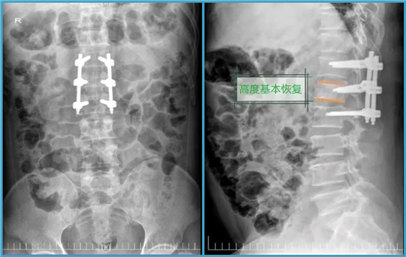

手术前 手术后

作为家庭支柱的李先生,无法接受不能做重活等后果。同时,他在化龙镇没有医保,家庭也不富裕,无力承担较高额度的手术费用。结合患者的实际情况,为了帮助患者节省医疗费用,最大限度地“修复”患者腰椎,刘伯昊主任团队决定为其施行传统开放手术——“后路切开复位经椎弓根内固定术”。经过近两小时的手术,患者爆裂、粉碎的椎骨高度恢复90%以上,破碎的骨片也复位了,神经没有受到任何损伤。术后,经过半个月的精心护理,李先生顺利康复出院。